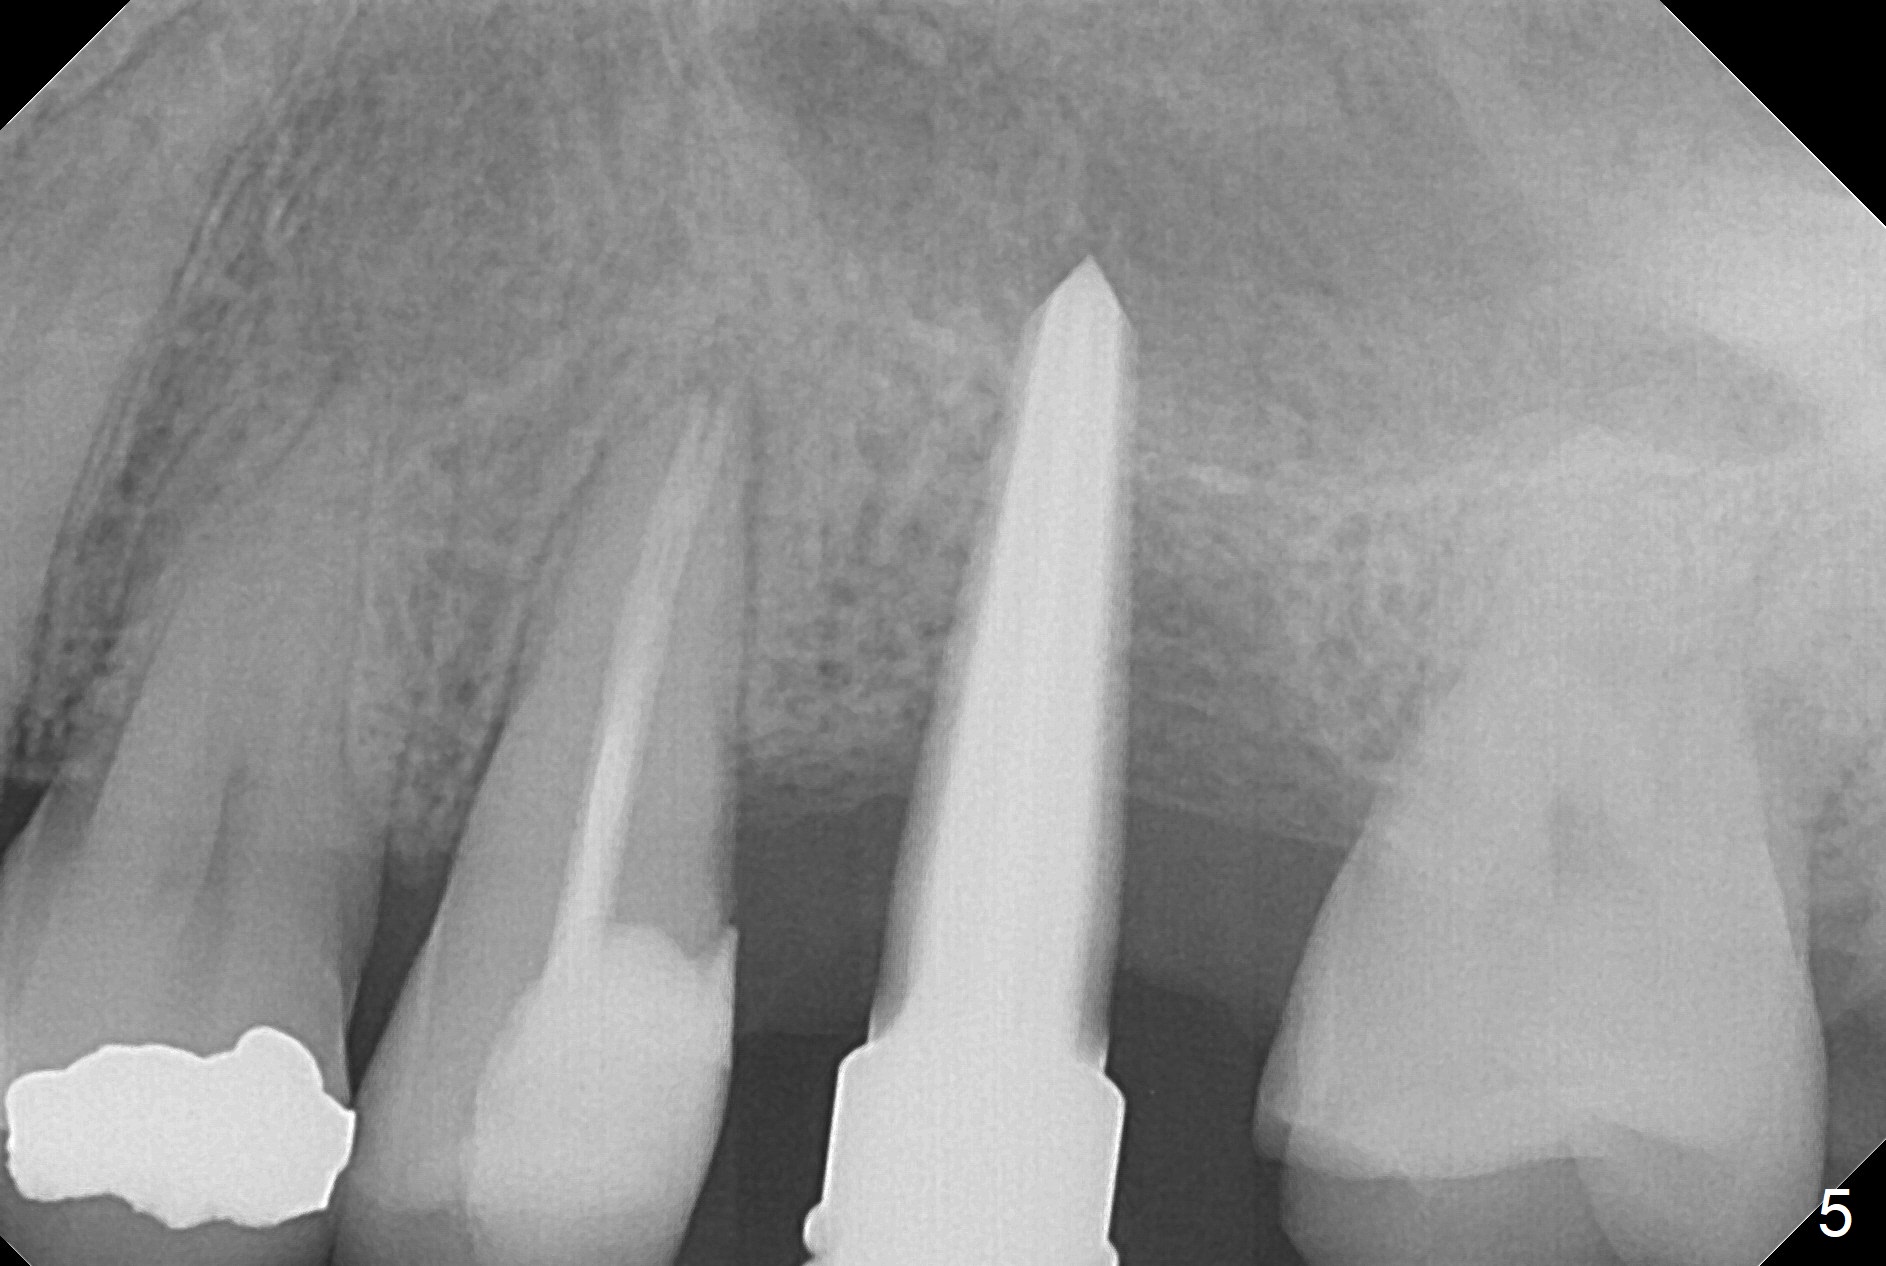

After extraction of the distobuccal residual root of the tooth #14 (Fig.1 arrow), the gingiva around the socket does not look like the keratinized one (Fig.2 *). An osteotomy through the distobuccal socket would seem too buccal for immediate implant. The palatal gingiva feels too tough to be stretched. An incision is made (Fig.3 dashed line); with elevation, the thick flap is transferred buccally (curved arrow). An osteotomy is initiated in the palatal bone with 1.5 mm drill, followed by Magic Expanders until 4.3 mm for 11 mm (Fig.4,5). Following Magic Drill 3.8x13 mm, the sinus membrane is found to be perforated. The latter is repaired with Osteogen plug. A 4.5x9 mm IBS implant is placed with 50 Ncm (Fig.6). Osteogen plug and allograft (Fig.7 *) are inserted into the remaining distobuccal socket (reduced after bone expansion). When a 5.5x4(4) mm abutment is placed, the transferred flap appears to be adapted to the distobuccal defect (Fig.8 *). Later one suture is placed for fixation. After provisional insertion, periodontal dressing is applied. Nine days postop, the periodontal dressing dislodges. When the loose provisional is removed for recementation, the flap seem to have healed (Fig.9 *). The gingiva heals around the abutment 5 months postop (Fig.9); the distal socket appears to heal while the bone graft remains at the crest (Fig.11,12). When #30 develops buccal abscess, the patient masticates on the left, leading to loss of composite at #13 (Fig.14); in fact the abutment at #14 is incompletely seated.